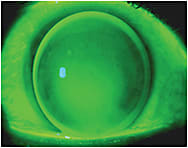

Last month, I addressed using small-diameter, steep corneal GP lenses to manage irregular astigmatism caused by small, centrally located keratoconic cones. But what design should you choose when the keratoconic cone is larger (oval cone, Figure 1), very large (globus cone), or is located away from the visual axis (Figure 2)? What is the best way to manage other causes of irregular astigmatism that result from other conditions, including corneal surgery (Figure 3) and trauma?

Figure 3. Status post-radial keratotomy.